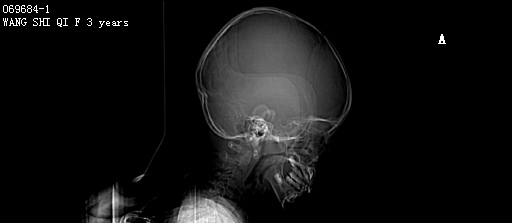

PED5204:F,3y。抽搐10分钟。

女,3岁。抽搐10分钟。 初步诊断:惊厥。 今行头部CT扫描,图像如下:

右侧颞枕叶可见较大囊性占位,边缘光整,并与同侧侧脑室相通,脑室扩大,考虑右侧颞枕叶蛛网膜囊肿并脑穿通畸形?建议结合临床,MRI检查。

脑积水,右侧脉络膜乳头瘤?建议核磁